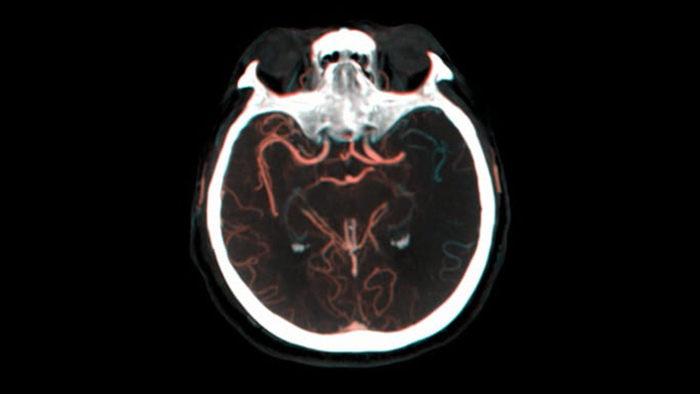

Ver llenado colateral

Visualización del llenado colateral

La vista dual para ver los volúmenes de TC de haz cónico de fase temprana y tardía uno al lado del otro mejora la identificación de la penumbra y permite la visualización del relleno colateral.